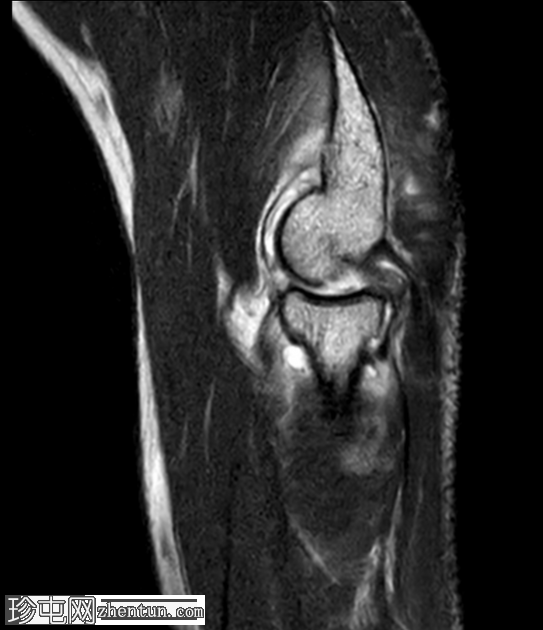

轴位

T1加权像

桡骨头及桡骨颈可见骨髓水肿,前内侧关节内部分可见低信号骨折线,符合桡骨头无移位骨折。

肱骨远端外侧髁/肱骨小头也可见明显的骨髓水肿。伴有皮质不规则、凹陷及正常轮廓消失,提示骨小梁嵌顿。

位于水肿骨内的这处骨损伤(奥斯本-科特里尔损伤)代表的是真正的撞击性骨折,而非常见的正常解剖假性缺损。

桡骨近端周围存在广泛的软组织水肿和液体信号,提示环状韧带损伤。

另可见大量关节积液。